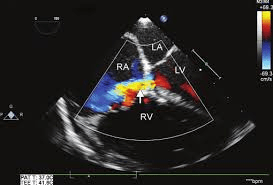

The following image is a four-chamber view zoomed on the mitral valve during diastole. Which velocity is greater, A or B

Velocity at B is greater than A

In this view blood flow is moving from the left atrium to the left ventricle. Aliasing can be appreciated at point B, where despite the flow going away from the probe, it is represented as going toward the probe (red). This is due to the fact that flow acceleration occurred and the velocity is exceeding the nyquist limit.